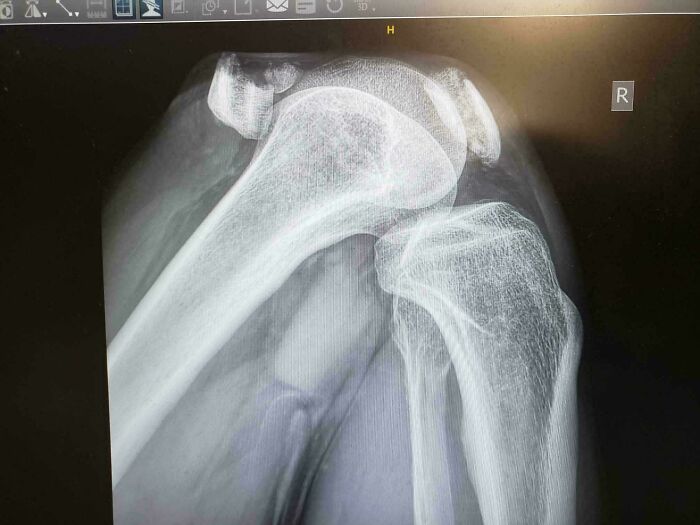

#68

Broken Kneecap

X-ray image of a human shoulder joint showing bones and possible extra finger anatomy details

Bro slipped and knee-dropped to the floor. After getting his knee bolted back together, a staph infection almost ended him. He’s had to have three surgeries for this already. He briefly thought he was going to need a bone graft too, but thankfully it turned out not. Don’t underestimate those slippery floors, folks.

CosmicSqueak Report